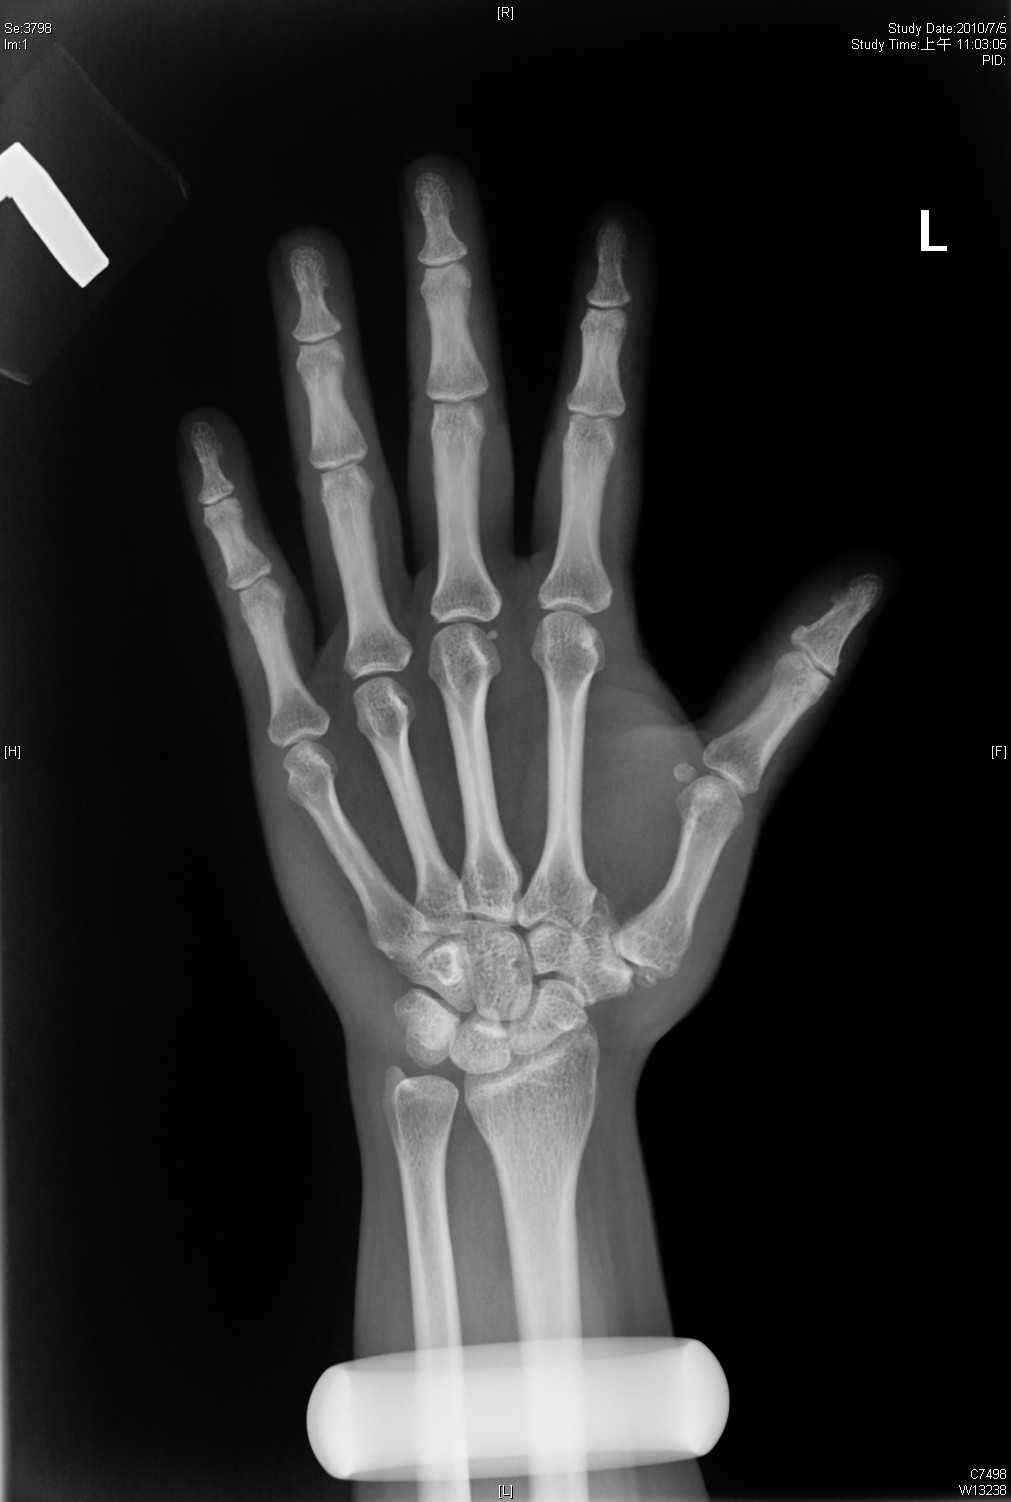

Big Bad Basal joint OA with subluxation Basal Joint Oa The universal joint at the base of the thumb, between the metacarpal and trapezium bones, often becomes arthritic as people get older. This condition is a degeneration of cartilage in the joints at the base of the thumb, collectively. It is osteoarthritis, which is loss of the smooth. Up to 15% of the population older than 30 years suffers from. Basal Joint Oa.